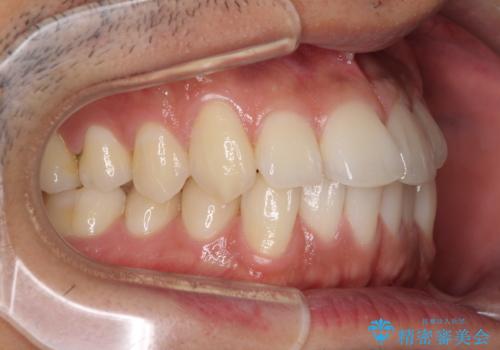

前歯のデコボコを治したい インビザライン矯正治療

- 前歯のデコボコを治したいとのことで来院された患者様です。

上下顎ともに歯列全体の後方移動とIPR(歯と歯の間を削る)によってデコボコが解消するように設計し、インビザラインにより治療を行うこととしました。

毎日22時間以上しっかりとマウスピースを装着していただいたので、スムーズに治療が進みました。歯と歯の間を削ることでうまくスペースコントロールでき、1年強で終えることができました。